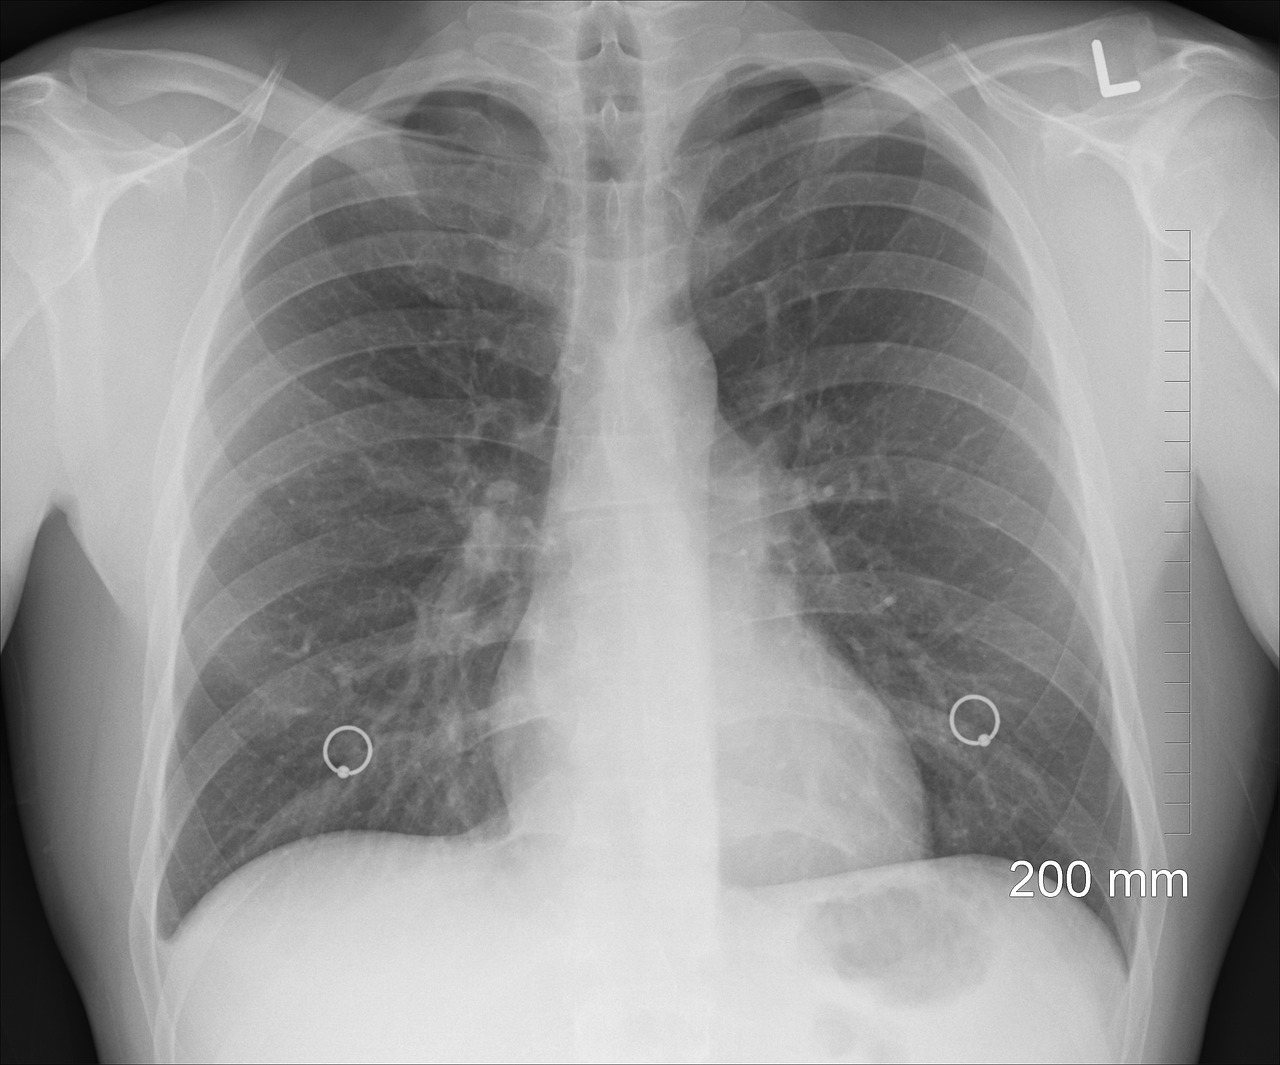

COPD의 주요 증상으로는 만성 기침, 가래, 호흡곤란이 있습니다. 초기에는 운동 시에만 호흡이 어려울 수 있지만, 질환이 진행됨에 따라 일상적인 활동에서도 호흡곤란을 느낄 수 있습니다. 또한, 흉부 압박감, 피로감, 체중 감소 등의 증상도 나타날 수 있습니다.. 만성 폐쇄성 폐질환(COPD)을 진단하는 데는 증상 외에도 여러 가지 방법이 있습니다. 아래는 COPD를 진단하는 주요 방법들입니다:폐 기능 검사(Spirometry):폐 기능 검사는 COPD를 진단하는 가장 중요한 검사 중 하나입니다. 이 검사는 환자가 최대한 깊게 숨을 들이마신 후 빠르고 강하게 내쉬는 동안의 공기 흐름을 측정합니다. 이를 통해 폐의 용량과 공기 흐름의 제한 정도를 파악할 수 있습니다. 특히, FEV1(첫 1초 동안의 강제 호기량)와 FVC(강제 폐활량)의 비율이 중요한 지표가 됩니다.흉부 X선 촬영:흉부 X선 촬영은 폐와 심장의 상태를 시각적으로 확인하는 방법입니다. COPD 환자의 경우, 폐의 과다 팽창이나 폐렴 등의 합병증을 확인할 수 있습니다. 또한, 이 검사를 통해 결핵이나 폐암과 같은 다른 질환을 배제할 수도 있습니다.CT(컴퓨터 단층촬영) 스캔:CT 스캔은 보다 정밀하게 폐의 구조를 확인할 수 있는 검사입니다. COPD의 경우, 폐포의 파괴나 기관지의 변화를 더 명확하게 관찰할 수 있습니다. 특히, 폐기종(Emphysema)이 의심되는 경우 유용합니다.혈액가스 분석(Arterial Blood Gas Analysis):이 검사는 혈액 내 산소와 이산화탄소의 농도를 측정하여 호흡 기능을 평가합니다. COPD 환자의 경우, 산소 포화도가 낮고 이산화탄소 농도가 높을 수 있습니다. 이를 통해 호흡 부전의 정도를 파악하고 산소 치료의 필요성을 평가할 수 있습니다.심전도(EKG) 및 심장초음파:COPD는 심장에 영향을 줄 수 있기 때문에, 심전도와 심장초음파를 통해 심장 기능을 평가하는 것도 중요합니다. 특히, 폐고혈압이나 심부전 등의 합병증을 확인할 수 있습니다.알파-1 항트립신 결핍 검사알파-1 항트립신 결핍은 유전적인 원인으로 COPD를 유발할 수 있습니다. 이 검사는 혈액을 통해 알파-1 항트립신의 수준을 측정하여 결핍 여부를 확인합니다. COPD의 진단은 다양한 검사를 통해 종합적으로 이루어집니다. 증상뿐만 아니라, 위의 다양한 검사를 통해 정확한 진단을 받고 적절한 치료를 받는 것이 중요합니다. 정기적인 건강 검진과 폐 기능 검사를 통해 조기에 발견할 수 있습니다